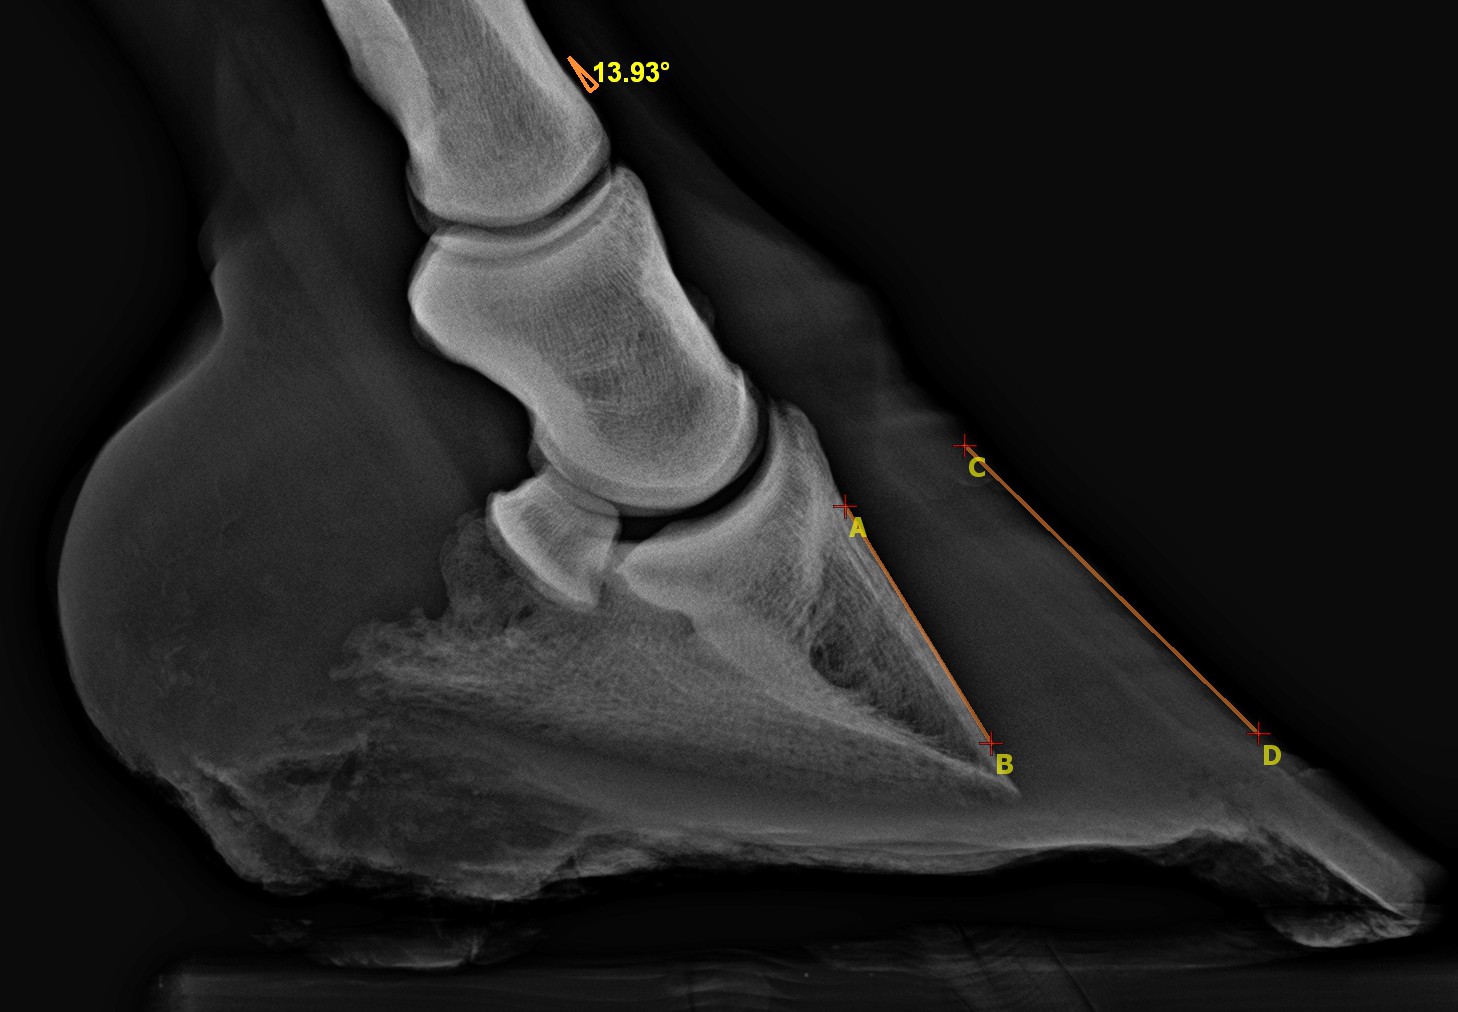

Súlyos fokú patairha gyulladás miatt kialakuló, nagyfokú, 14 fokos rotáció.